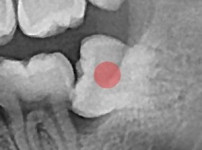

부분 매복 사랑니 발치

부분 매복 사랑니